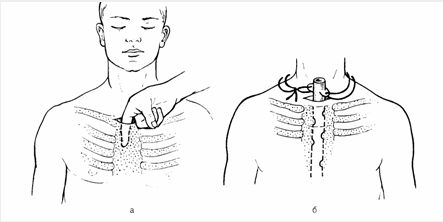

Kəskin mediastinit şübhəsi olan xəstə təcili xəstəxanaya yatırılır, diaqnoz qoyulan kimi aktiv dəstək, antibiotikoterapiya başlanılır və cərrahi müalicə həyata keçirilir. Kəskin mediastinitin müalicəsində cərrahi müalicə əsas tədbirdir və iki məqsədlə yerinə yetirilir: irinliyin sanasiyası-drenajı və səbəbin aradan qaldırılması (Şəkil 12).

Şəkil 12. Divararalığının drenajı

Sanasiya-drenaj üçün divararalığına yuxarıdan, transsternal, transtorakal yollarla müdaxilə etmək olar. Səbəbi aradan qaldırmaq üçün edilən əməliyyatlar səbəbdən asılı olaraq dəyişir.